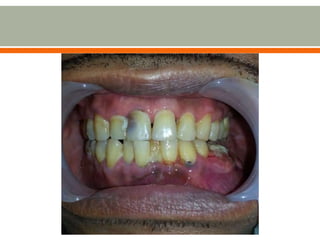

 Here, a 55-year-old male patient was presented with a

complaint of painful swelling on the mandibular left 2nd

premolar area.

 Left mandibular mass

2 years PTC

 patient underwent tooth extraction of a carious left